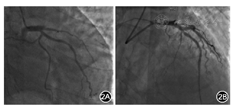

患者男,63岁。因"突发胸痛2 h"入院。患者晨起活动时突发剑突下压榨性疼痛,持续不缓解,伴全身大汗淋漓,无其他部位放射痛,无头痛、晕厥,无咳嗽、咯血,无恶心、呕吐,无呼吸困难。既往有高血压病史10余年,糖尿病病史3年。入院体检:体温36.5℃,脉搏63次/min,呼吸17次/min,血压118/76 mmHg(1 mmHg=0.133 kPa)。神志清,精神稍萎靡,痛苦面容,心肺腹体检未见明显异常。急诊查心电图示:窦性心律;V1~V4导联R波递增不足;V5、V6导联ST段上斜型压低伴有J点下移;V2~V4导联T波高尖;aVR导联ST段稍抬高(图1);肌钙蛋白I<0.10 μg/L、肌酸激酶同工酶<2.00 μg/L、肌红蛋白<20.00 μg/L;D-二聚体0.16 mg/L;N末端B型利钠肽前体4 560 ng/L。考虑de Winter综合征,拟诊"急性冠状动脉综合征(ACS)"收入冠心病重症监护室(CCU),予阿司匹林300 mg、替格瑞洛180 mg口服后行冠状动脉造影(CAG)示:开口正常,左冠状动脉主干(LM)未见明显狭窄;左冠状动脉前降支(LAD)近段闭塞,前向血流心肌梗死溶栓治疗(TIMI)0级(图2A);左回旋支(LCX)正常,前向血流TIMI 3级;右冠状动脉(RCA)中段斑块,前向血流TIMI 3级;于LAD病变处行经皮冠状动脉介入(PCI)治疗,置入支架一枚,术后LAD血流恢复,前向TIMI 3级(图2B)。术后约2h复查心电图提示:窦性心律,V4~V6导联下压的ST段恢复至基线附近,V2~V5导联高尖T波变低,aVR导联ST段也恢复至正常水平(图3)。